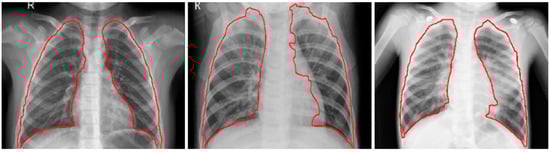

Figure 2.

Detected boundaries in sample pediatric CXRs.

The CXRs contain regions other than the lungs that do not contribute to diagnosing pneumonia. Under these circumstances, the model may learn irrelevant feature representations from the underlying data. Using an algorithm based on anatomical atlases [] to automatically detect the lung ROI can avoid this. A reference set of patient CXRs with expert-delineated lung masks are used as models [] to register with the objective pediatric CXR. When presented with an objective chest radiograph, the algorithm uses the Bhattacharyya distance measure to select the most similar model CXRs. The correspondence between the model CXRs and objective CXR is computed by modeling the objective CXR with local image feature representations and identifying similar locations by applying SIFT-flow algorithm []. This map is the transformation applied to the model lung masks to transform them into the approximate lung model for the objective chest radiograph. The lung boundaries are cropped to the size of a bounding box to include all the lung pixels that constitute the ROI for the current task. The baseline data (whole CXRs) and the cropped bounding box are resampled to 1024 × 1024 pixel dimensions and mean normalized to assist the models in faster convergence. The detected lung boundaries for the sample pediatric CXRs are shown in Figure 2.